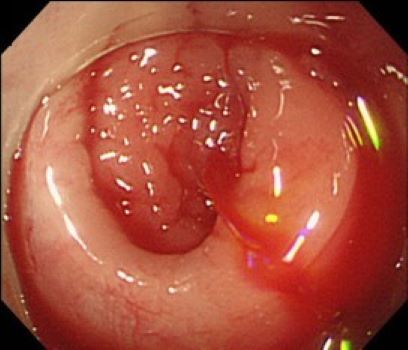

大腸憩室出血の内視鏡画像:憩室内のneckの血管からの活動性出血

出典

img

1: 著者提供